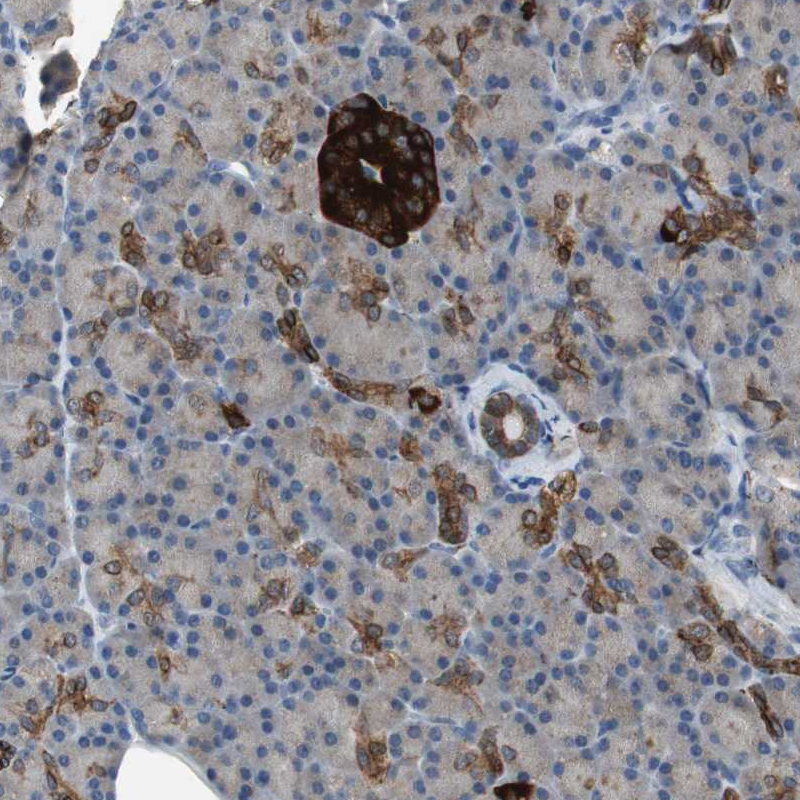

Immunohistochemistry analysis in human pancreas and skeletal muscle tissues using HPA006900 antibody. Corresponding PTPRN2 RNA-seq data are presented for the same tissues.